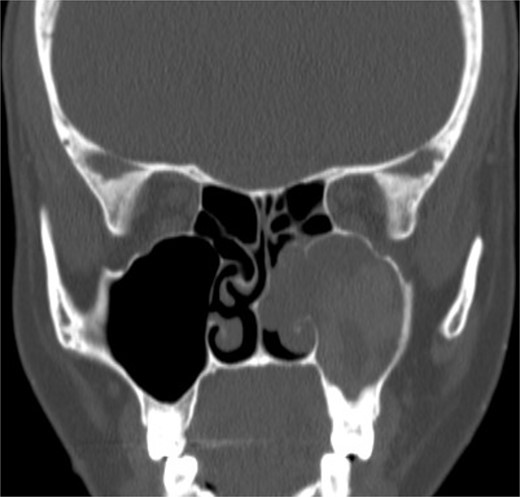

Coronal NCCT image of the paranasal sinuses showing isolated left complete heterogenous maxillary sinus opacification with obstructed left osteomeatal complex.

Intra-operative endoscopic view showing (A) polyps in the left osteomeatal complex with (B and C) fungal mud and mucin.